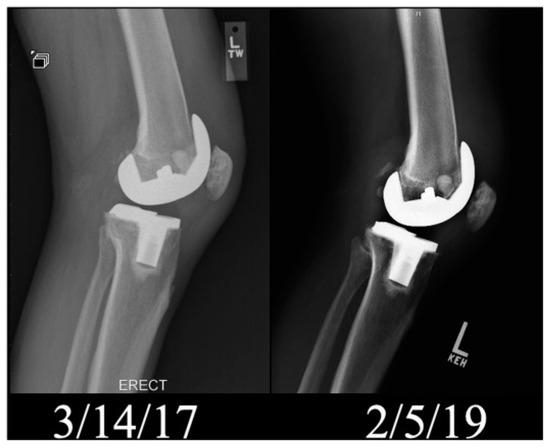

- Lieberman, E.G.; Barrack, R.L.; Schmalzried, T.P. Suspected Metal Allergy and Femoral Loosening After Total Knee Arthroplasty: A Diagnostic Dilemma. Arthroplast. Today 2021, 7, 114–119. [Google Scholar] [CrossRef] [PubMed]